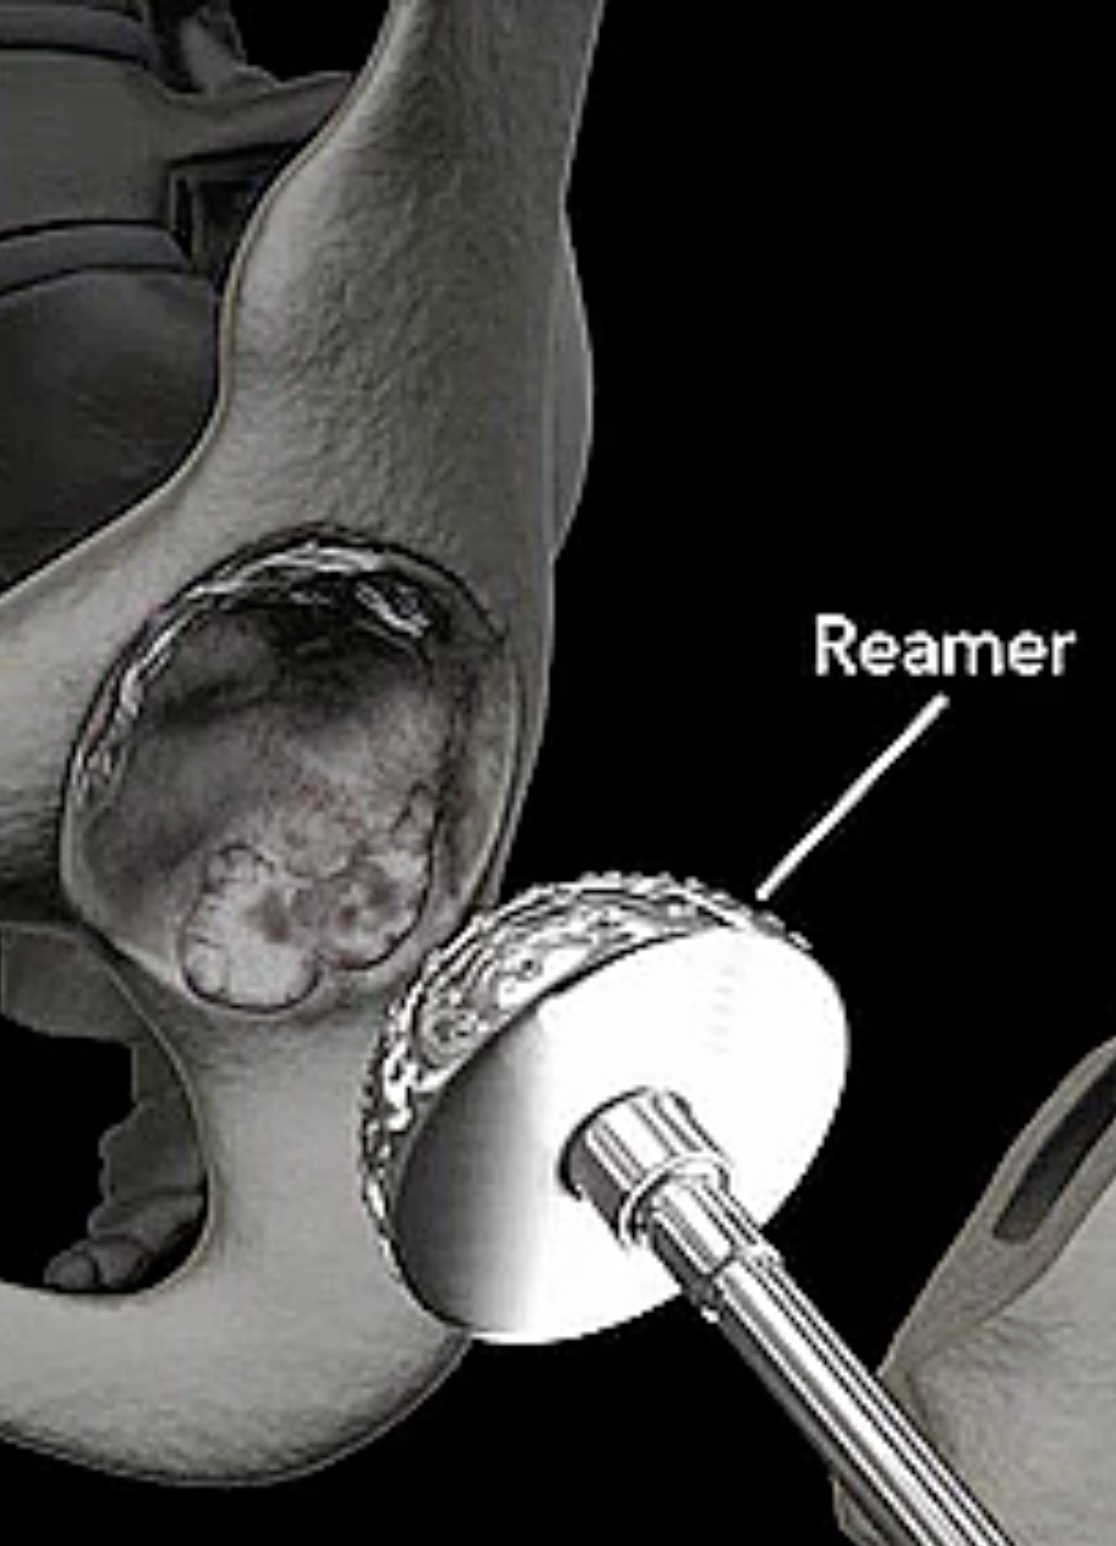

- 人工髋关节置换术(视频) BuGu ,2020-01-08

- 骨性关节炎是人工关节置换术的首选适应征,其它依次为骨无菌性坏死(如股骨头坏死等)、某些髋部骨折(如股骨颈骨折)、类风湿性关节炎、创伤性关节炎、良性和恶性骨肿瘤、强直性脊柱炎等。总之,只要有关节破坏的X线征象,伴有中度至重度持续性的关节疼痛和功能障碍,而且通过其他各种非手术治疗都不能得到缓解的疾病,都.....